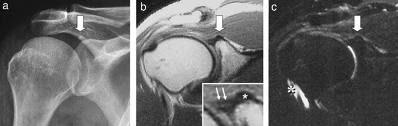

La neuralgia amiotrófica es una entidad clínica que se caracteriza por la aparición de un dolor intenso unilateral del hombro, de comienzo brusco.

Tras ceder el dolor aparece un cuadro de debilidad y atrofia de la musculatura dependiente de los nervios del plexo braquial lesionados.

Los nervios más afectados es el circunflejo, supra escapular, torácico largo, musculo cutáneo y radial.